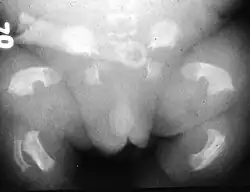

Radiogram of a baby born with thanatophoric dwarfism

Infants with this condition have disproportionately short arms and legs with extra folds of skin. Other signs of the disorder include a narrow chest, small ribs, underdeveloped lungs, and an enlarged head with a large forehead and prominent, wide-spaced eyes. Thanatophoric dysplasia is a lethal skeletal dysplasia divided into two subtypes. Type I is characterized by extreme rhizomelia, bowed long bones, narrow thorax, a relatively large head, normal trunk length and absent cloverleaf skull. The spine shows platyspondyly, the cranium has a short base, and, frequently, the foramen magnum is decreased in size. The forehead is prominent, and hypertelorism and a saddle nose may be present. Hands and feet are normal, but fingers are short. Type II is characterized by short, straight long bones and cloverleaf skull.[1] It presents with typical telephone-handle shaped long bones and H-shaped vertebrae.

Infants with type 1 thanatophoric dysplasia also have curved thigh bones, flattened bones of the spine (platyspondyly) and shortened thoracic ribs. Note: Prenatal ultra-sound images of the ribs sometimes appear asymmetrical when in fact they are not. In certain cases, this has caused a misdiagnosis of osteogenesis imperfecta (OI) type II.